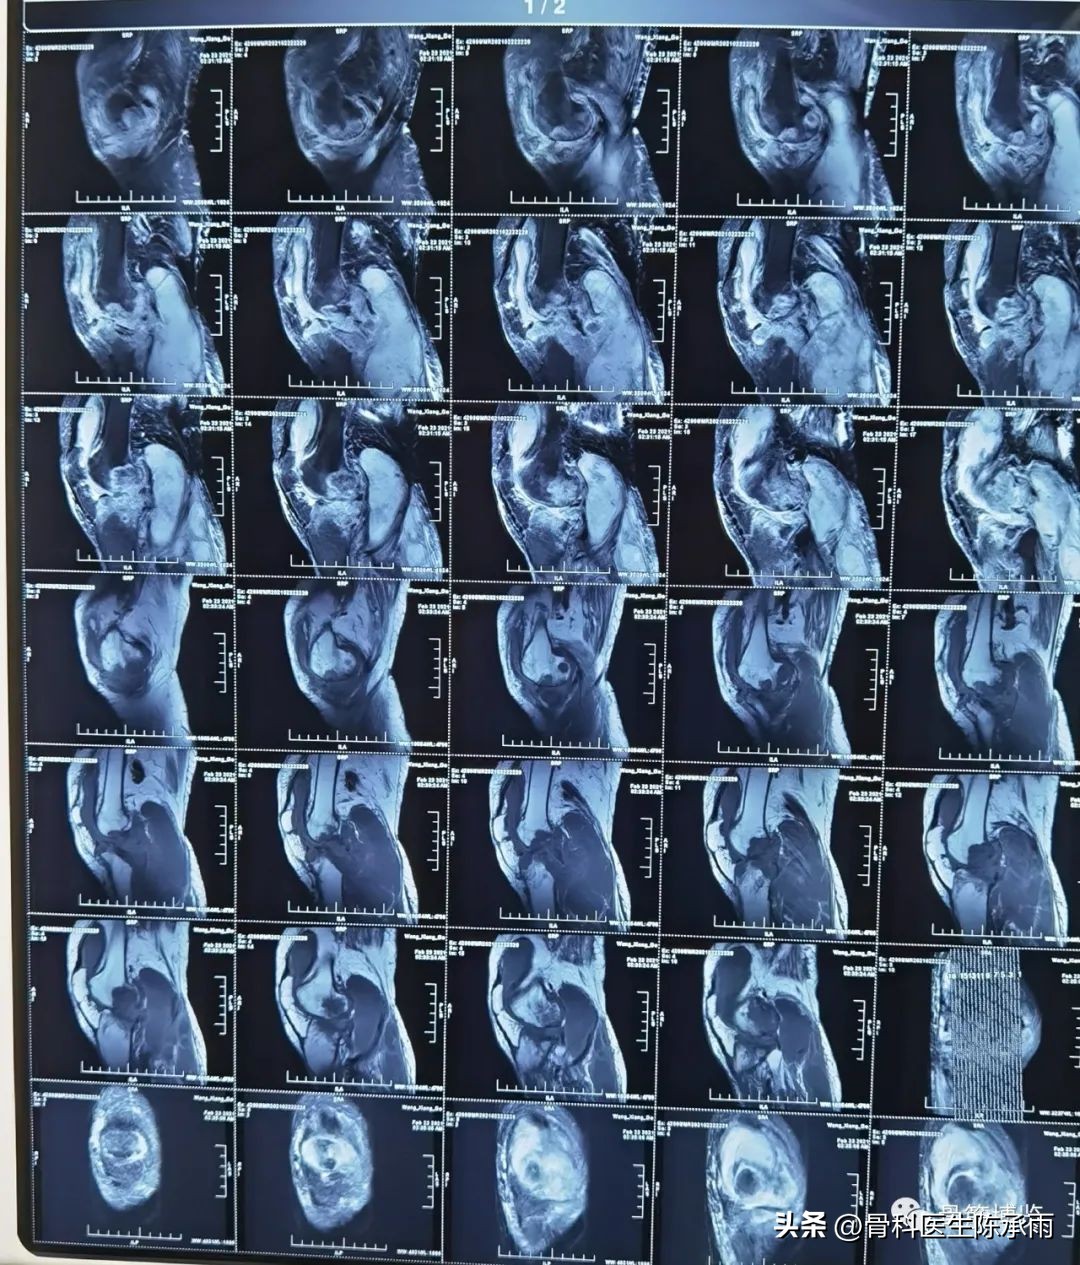

术前影像:

术中情况:关节破坏严重